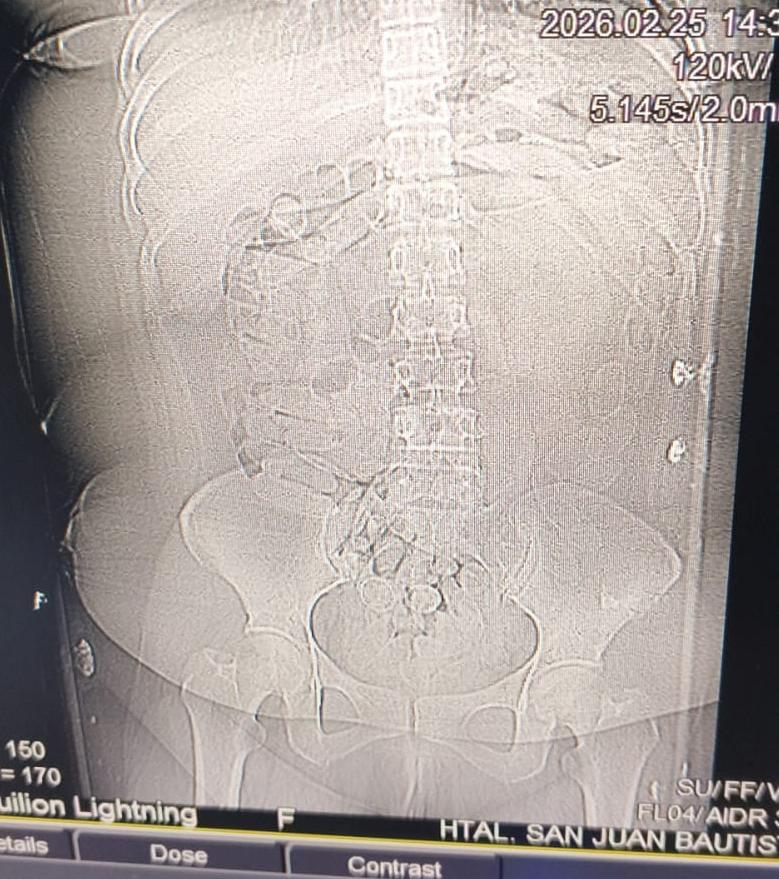

Tras los estudios correspondientes, se constató la presencia de cuerpos extraños en la zona abdominal y en la cavidad genital. Como resultado del seguimiento médico, se confirmó la evacuación de 90 cápsulas.